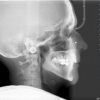

Tarkusehambad on kolmandad molaarid – asuvad kõige kaugemal hambakaares ja lõikuvad tavaliselt viimasena … kui nad üldse lõikuvad! Kas tarkusehambad peab eemaldama? Millal ja miks? Tarkusehammaste normaalseks lõikumiseks peab lõualuu tagumine osa – margo posterior ja ramus mandibulae piisavalt ja oluliselt kasvama, mahutamaks tarkusehambaid. Kui kasv selles lõualuu regioonis on ebapiisav, jäävad tarkusehambad peetunuks. Joonis 1.